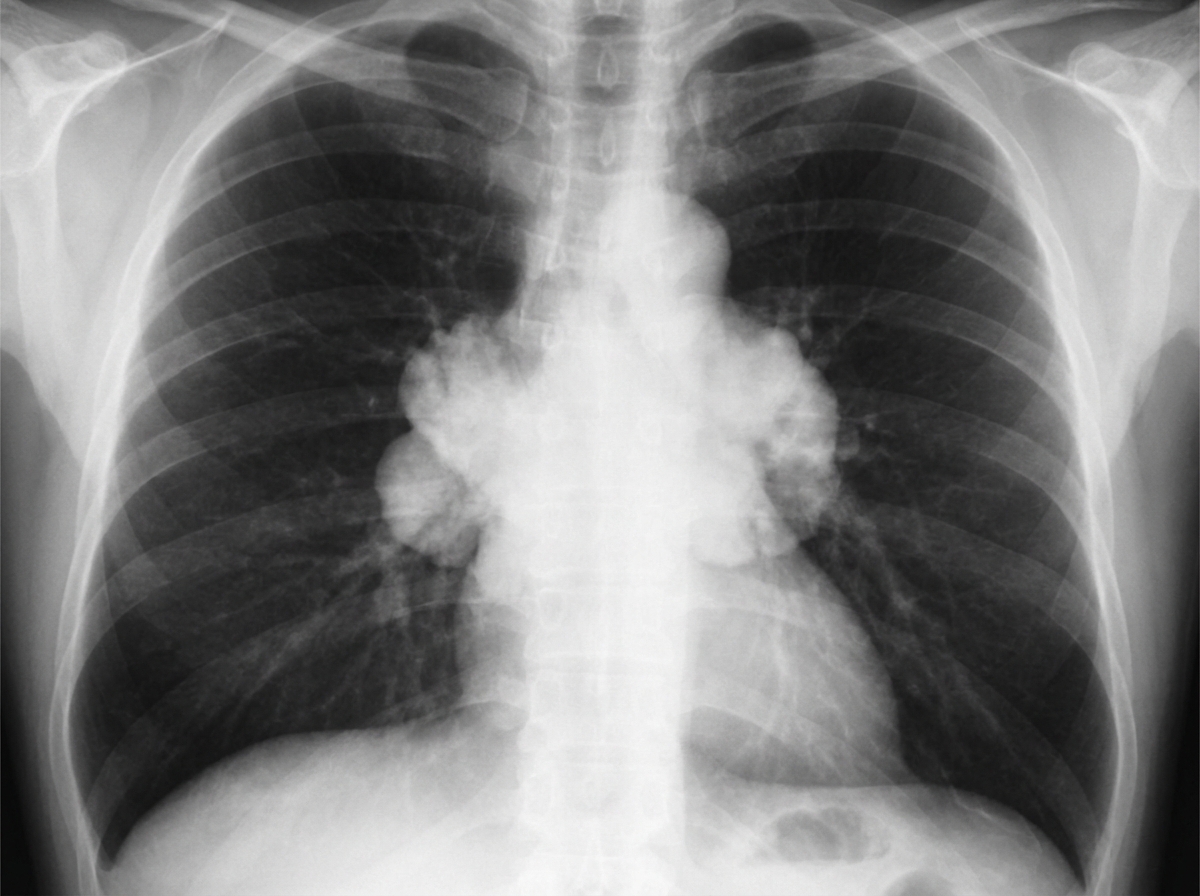

A 67-year-old man presents to his primary care physician because of a dry cough and shortness of breath for 2 months. He notes that recently he has had easy bruising of the skin without obvious trauma. He has a past history of chronic obstructive pulmonary disease and recently diagnosed with type 2 diabetes. Family history is non-contributory. He has smoked 1 pack of cigarettes daily for 35 years but quit 3 years ago. His temperature is 37.1°C (98.7°F), blood pressure is 170/80 mm Hg, and pulse is 85/min. On physical examination, the patient's face is round and plethoric and there are large supraclavicular fat pads. Breath sounds are diminished all over the chest without focal rales or wheezes. Chest X-ray is shown in the picture. Which of the following is the most likely etiology of this patient's condition?